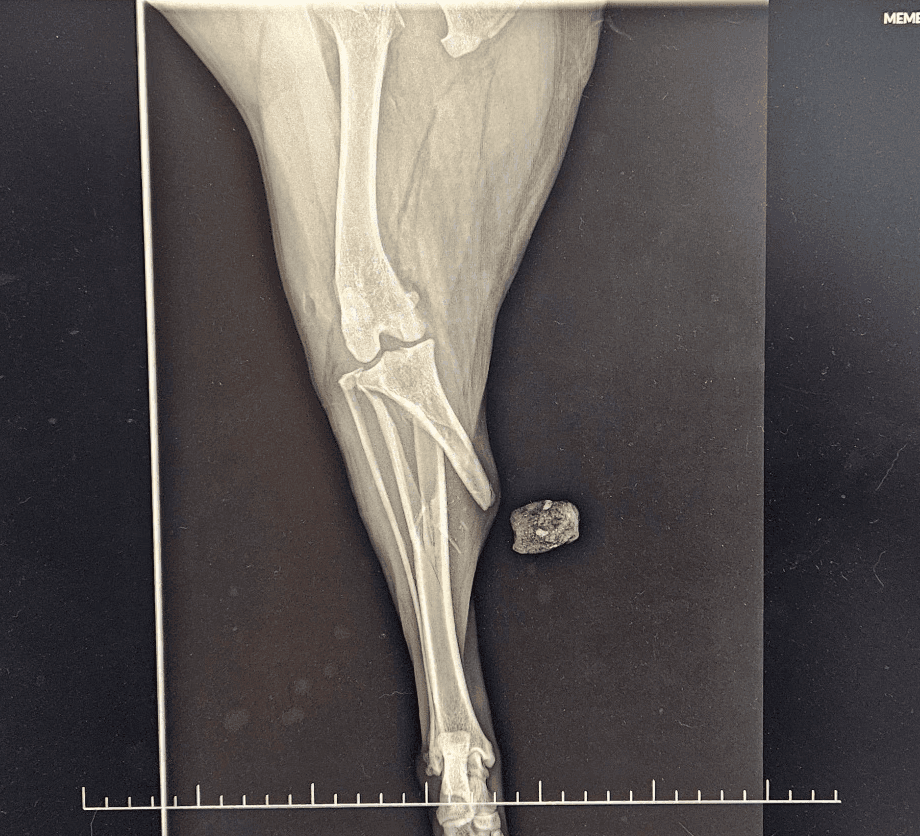

La prise en charge chirurgicale des fractures , des ruptures de ligaments croisés (TPLO, technique extra capsulaire) est réalisée aux Abymes où un bloc chirurgical lui est consacré spécifiquement.